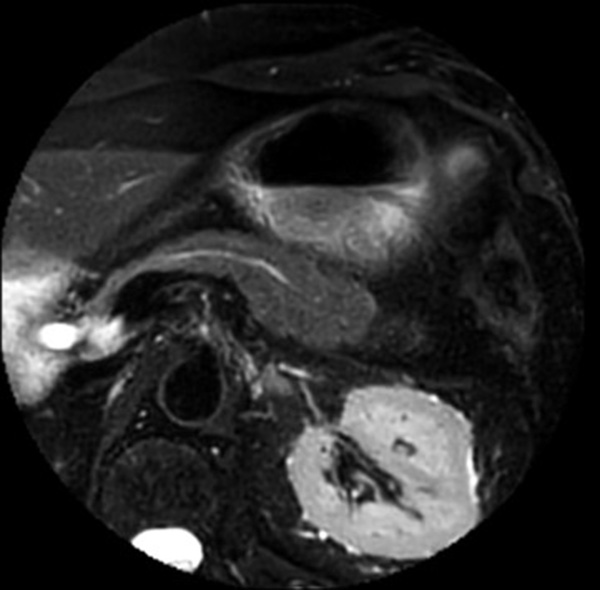

Pancreas imaging with dS Zoom